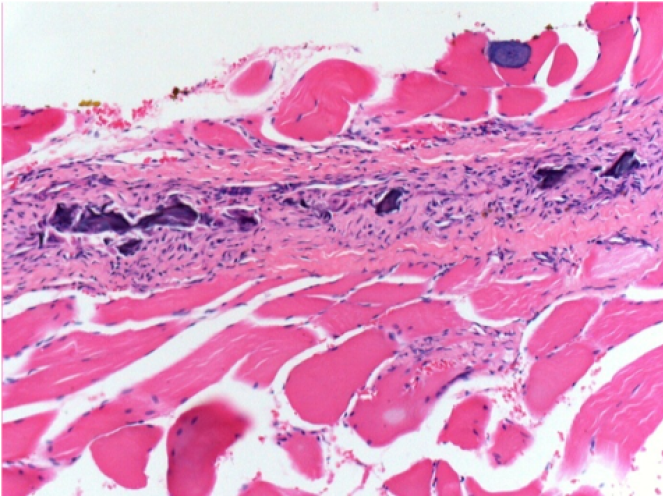

3 months (D90)after Endopeel Injection 0.1ml in the right pretibial muscle.

7 months (D210)after Endopeel IM Injection 0.1ml in the right pretibial muscle.

Complete Restitutio ad integrum after 7 months